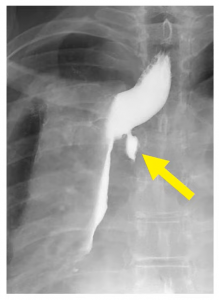

A Type 2 leak can be very large: